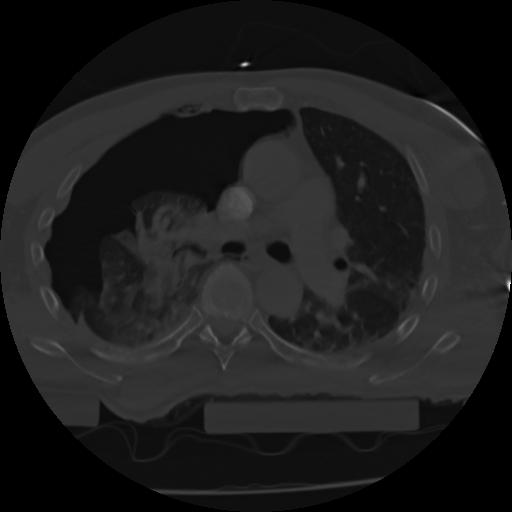

21 ANGIO,CE,Axial,3.0,ANGIO,,